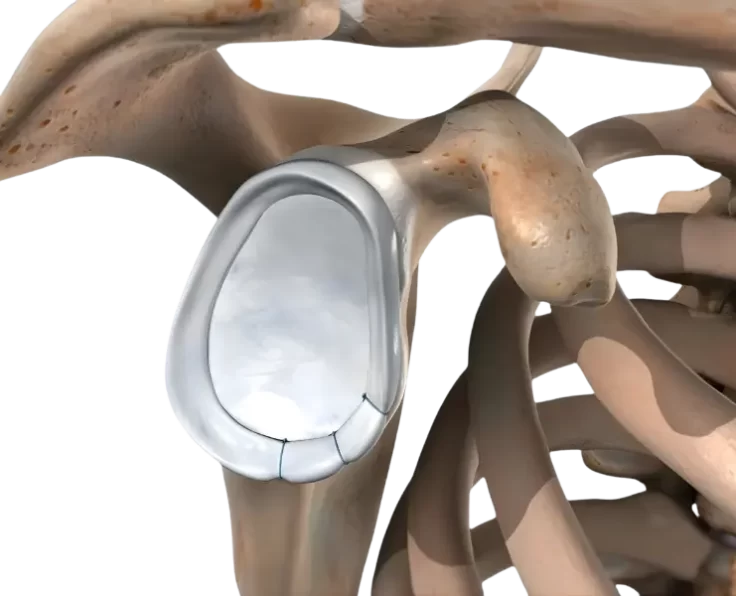

Short Stem Shoulder Replacement

The humeral implant is maintained in place by a "stem" that runs down the centre of the humerus in a typical shoulder replacement design (arm…

Resurfacing of Shoulder

The humerus (arm bone, which is the ball) and the glenoid (socket) are the two main components of your shoulder (socket).

Total Shoulder Replacement

Prime Shoulder Care is the most preferred clinic for Shoulder Replacement in Chennai.

Reverse Shoulder Replacement

This is a therapeutic option for shoulder arthritis that is also accompanied by rotator cuff problems.